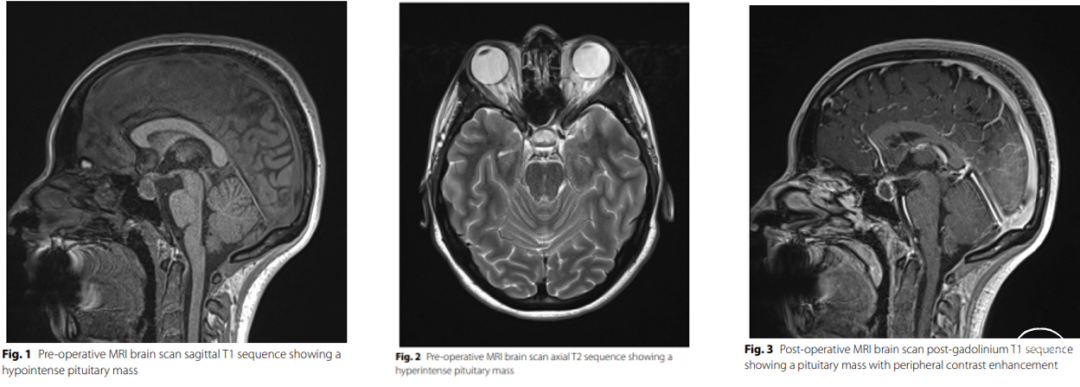

18日转脑外科,术前抗感染、激素补充治疗,20日行“经颅内镜鼻蝶垂体占位切除术”,引流出脓性液呈灰白色,未见明显肿瘤组织

查脓液培养未见异常

脓液病理无法明确

术后尿量在5000-7000ml左右,弥凝0.2mg,tid, 泼尼松片 早10mg中5mg